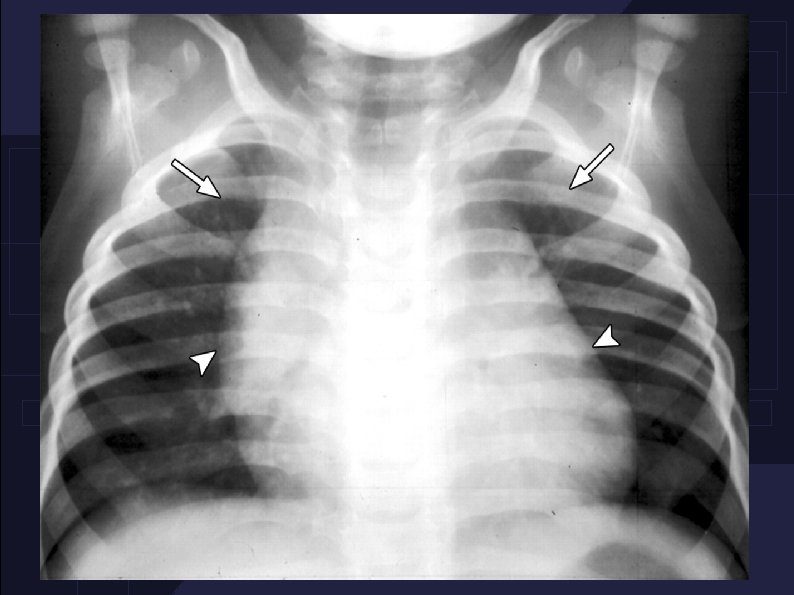

3 subtypes : Massive thymic hyperplasia. Common in infancy presents with compressive symptoms. Thymic hyperplasia assocaited with endocrine abnormalities.

Rebound thymic hyperplasia : The thymus gland regresses in size during times of severe stress then enlargres beyond normal. Seen following , severe burns , pneumonia , tuberculosis and malignancies.

Management : Close monitoring for 2 years. If thymic hyperplasia doesn't regress by 2 years , biopsies and resection are warranted.

Thymic rebound hyperplasia in an 11 -year-old girl with Hodgkin lymphoma.